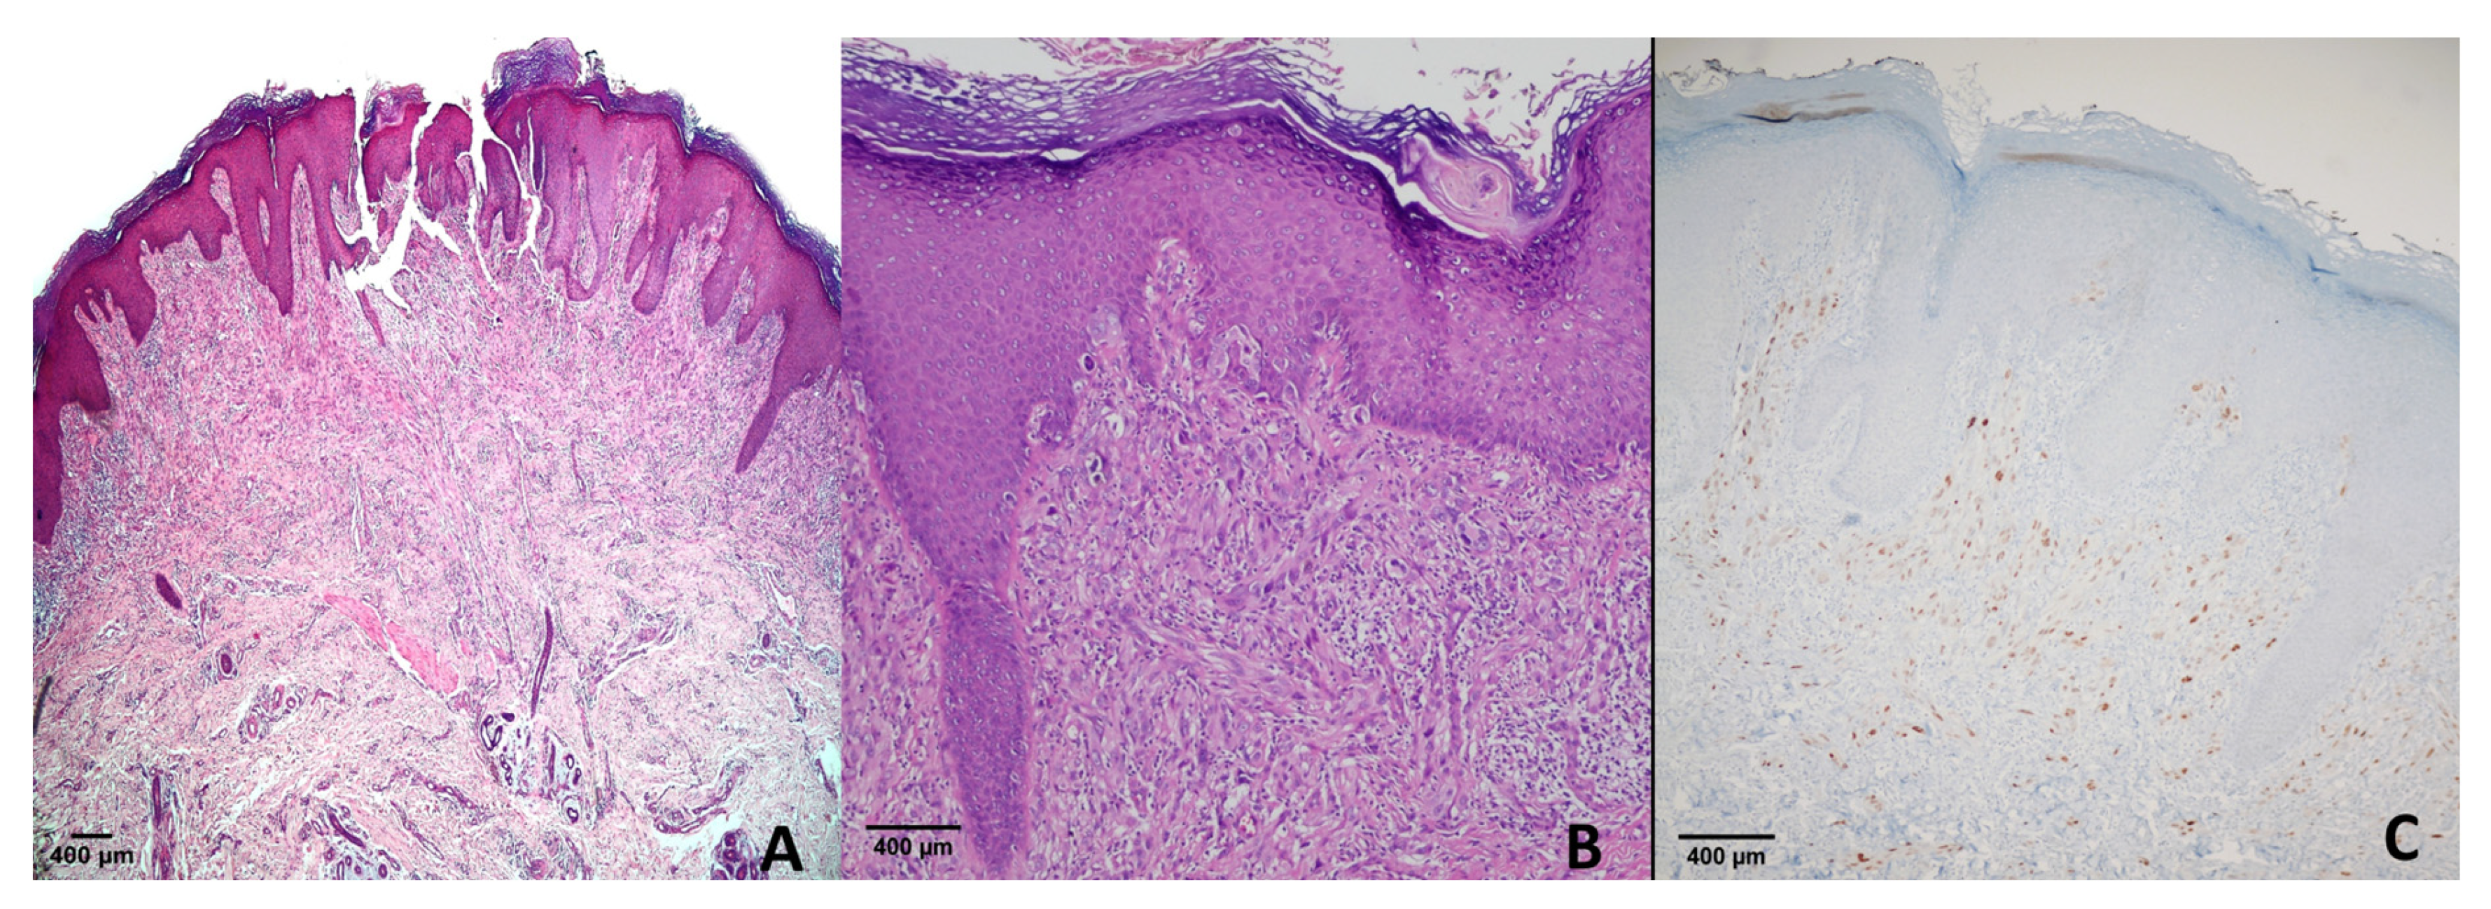

4.1. Dysplastic Nevi

| +1 | 0/12 | 0/40 | 2/27 | 0/5 | 1/15 | 0/23 | 1/11 | 0/12 |

| 0 | 0/12 | 1/40 | 24/27 | 5/5 | 14/15 | 23/23 | 10/11 | 10/12 |